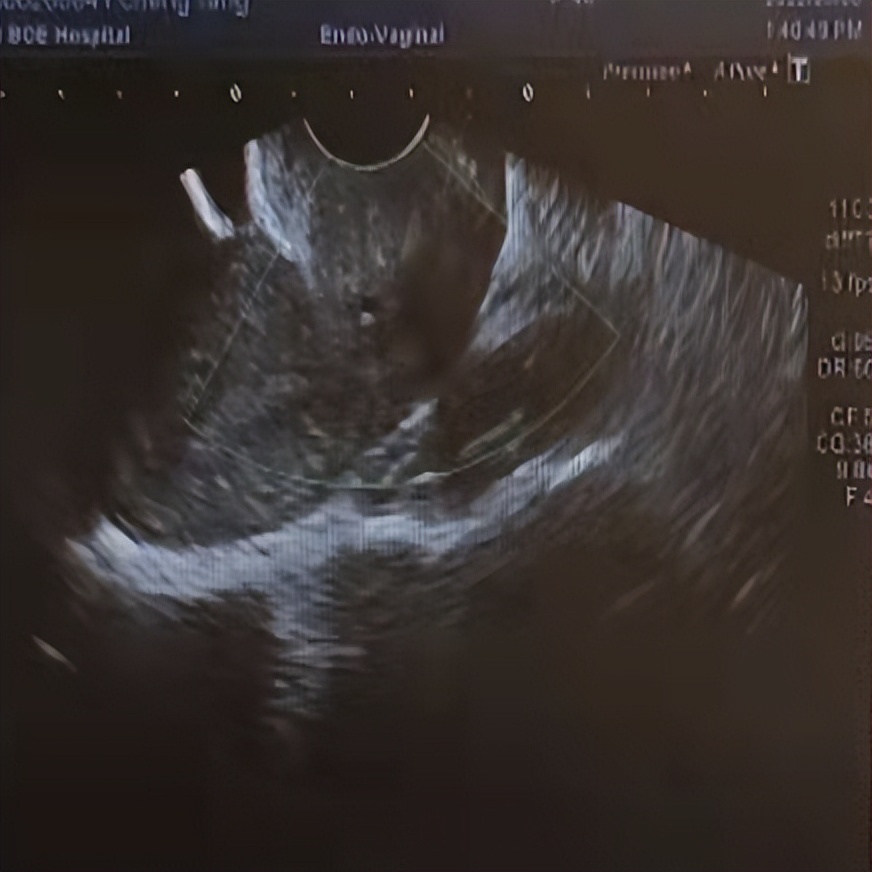

腔内彩超提示:右侧附件区可见14.5 *12.0*7.6cm巨大囊性肿物,建议患者尽快手术。程女士十分惧怕开腹手术,无法接受开腹手术后腹部留下巨大疤痕,但病情严重又不得不手术,这让她的心情一度非常沮丧。妇产科杨小东主治医师作为程女士的主管医师,在得知程女士内心的纠结后,精心为她制定了一套严密的单孔腹腔镜手术方案。得知将要进行的是只有一个小孔的微创手术,不仅能帮她解决卵巢囊肿问题,而且能避免腹部留下疤痕时,程女士非常惊喜。